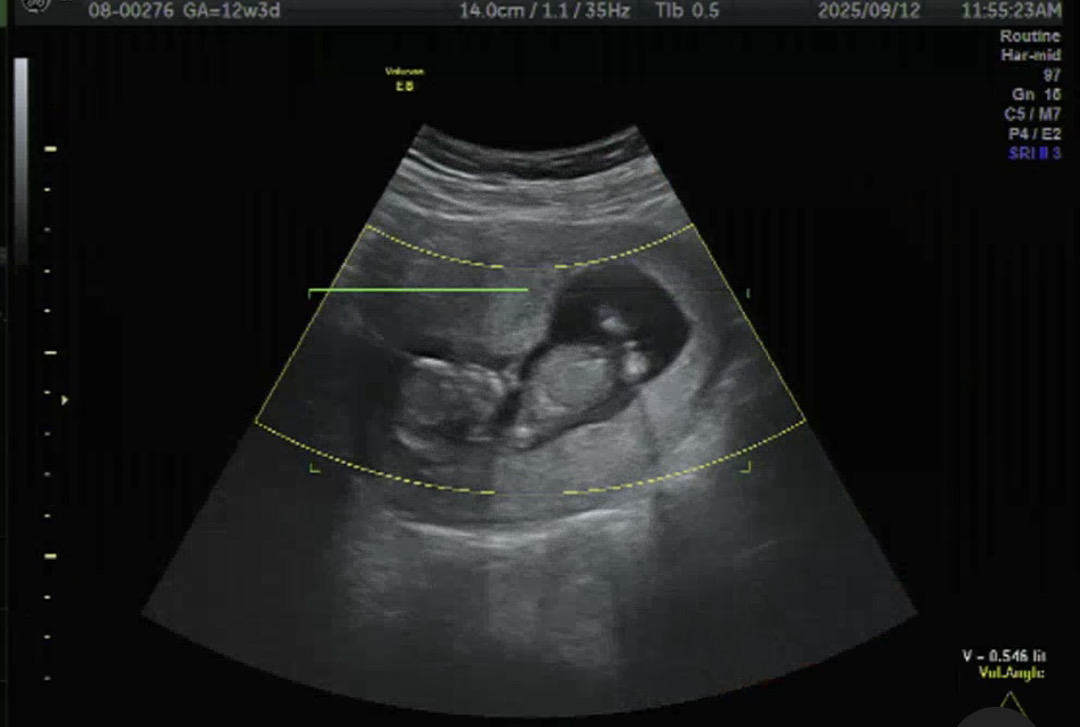

아들일까요? 딸일까요?

오늘 12주차에 1차 기형아검사하고 왔는데 다 정상범위안에 든다고는 해요ㅎㅎ그런데 확실하게 알고싶어 니프티검사도 진행하고 왔어요! 그리고 입체초음파보면서 선생님께서 살짝 힌트는 주셨는데 아들일까요? 딸일까요? 뭔가 보이시나용?!!!!